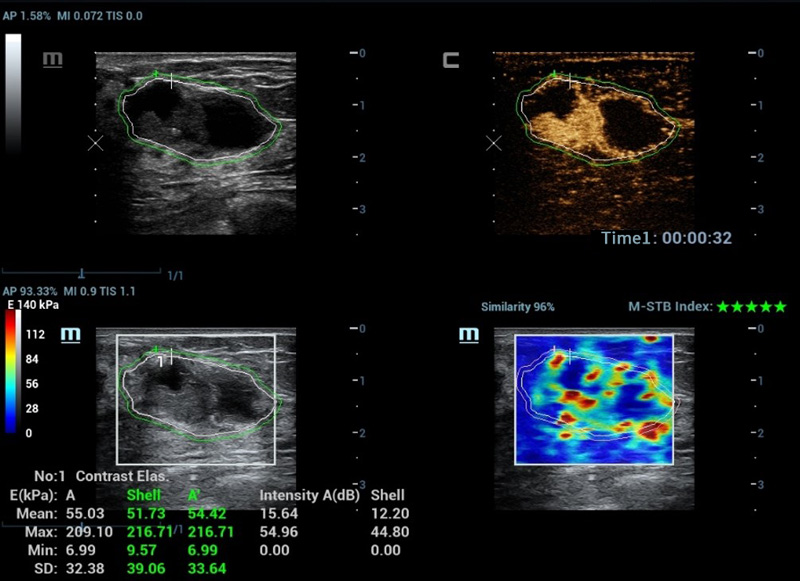

Ferramentas de anûÀlise multiparamûˋtrica M-Reference

M-Ref. C&E

M-Ref. C&E ã Tumor maligno de mama

M-Ref. C&E permitea exibi??o do contraste e da STE em um û¤nico plano para avalia??o comparativa de perfus?o e elasticidade.

M-Ref. E Compare

M-Ref. E Compare ã Tumor maligno de mama

M-Ref. E Compare oferece suporte û exibi??o tanto da elastografia por deforma??o em tempo real quanto da STE em um û¤nico plano para avalia??o da rigidez do tecido.